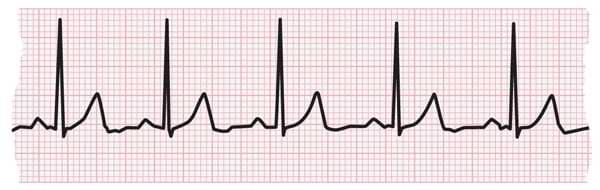

EKG strip showing a normal heartbeat

- Tachycardias are usually diagnosed by doing an electrocardiogram (EKG).